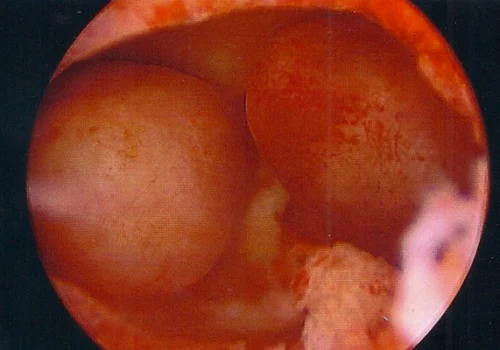

A 35 year old woman presented with primary infertility and significant intermenstrual spotting.

A pelvic ultrasound revealed two large endometrial polyps.

A Hysteroscopy and Polypectomy was performed.